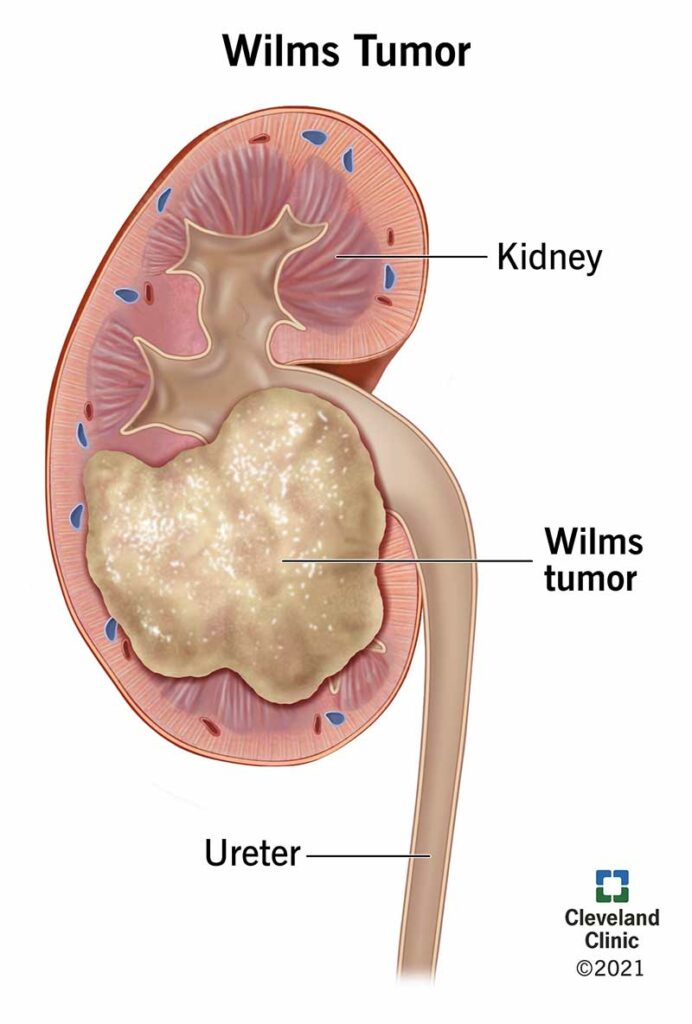

3. Wilms’ Tumor

- Number of People Afflicted Yearly: 1 in 10,000 children each year (about 500 to 650 in the U.S.)

- Area of Body Affected: Kidneys

- Is it Treatable?: Yes

- Survival Rate: High – 5-year survival rate is about 90%

Wilms’ tumor, also known as nephroblastoma, is the most frequent form of kidney cancer in children while being a relatively uncommon form of cancer in general. Wilms’ tumor is responsible for approximately five percent of all cases of cancer diagnosed in children.

Additionally, it is the most frequent form of abdomen cancer among children. Wilms’ tumor is almost always seen in children who are under the age of five, and the average age at which it is diagnosed is between three and four years.

Wilms’ tumor, fortunately, is very amenable to treatment despite the fact that it is regarded to be very frequent in youngsters.

In the United States, the five-year survival rate is fairly high, averaging at over ninety percent. Even for Stage IV and Stage V tumors that have a favorable histology, the survival rate is still very high at 86 and 87 percent respectively.